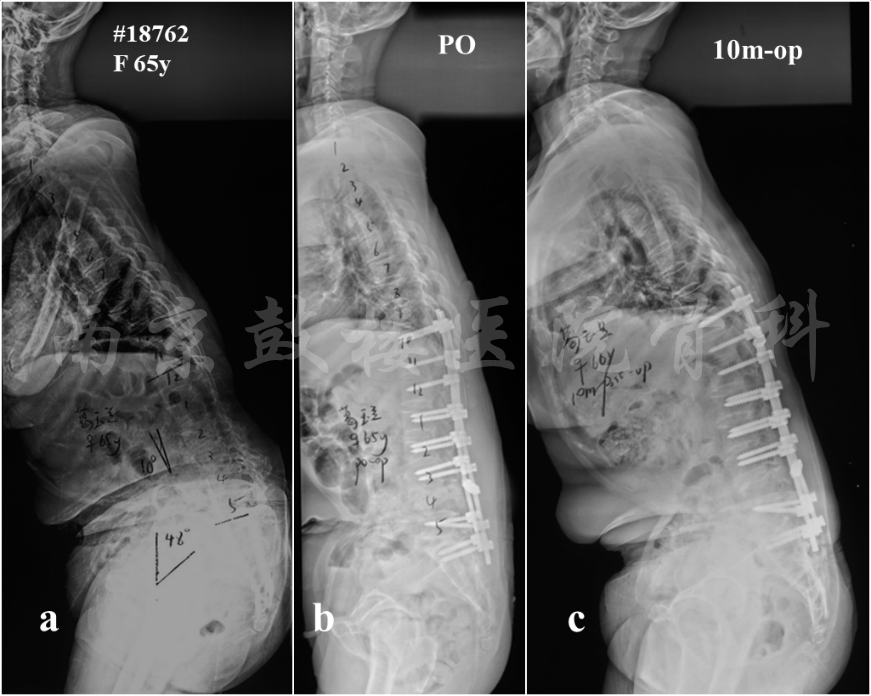

重建合理的矢状面平衡是预防远端内固定失败发生的重要手段。制定手术策略时,SVA应恢复到±5cm的范围内。患者可以通过骨盆后旋或膝关节的屈曲对矢状面失平衡进行代偿,导致骨盆倾斜角(PT)增大,因此术前评估矢状面序列时,患者应保持膝关节伸展,髋部和膝关节同时接触墙壁。术后重建矢状面时,应将PT控制在25°之内。而对于骨盆入射角(PI)较大的患者,则需要重建更大的腰椎前凸。综上,重建合理的矢状面平衡包括SVA<5cm, PT<20°以及PI-LL<±10°,可以有效预防术后远端内固定失败的发生(图4)。

图4 女,65岁。X片示矢状面严重失平衡(a),术前存在右下肢不全瘫;原定手术方案为L4 PSO截骨术,但术中出现MEP事件,且出血较多,因此未行三柱截骨,仅行后路减压及内固定术,术后X片示矢状面形态稍有改善,但是没有达到矫形的目标(b);术后10个月随访,患者躯干失平衡较术后加重,与术前类似(c)。该患者证明如果手术没有很好地重加矢状面形态,将是内固定失败和矫正丢失的重要危险因素